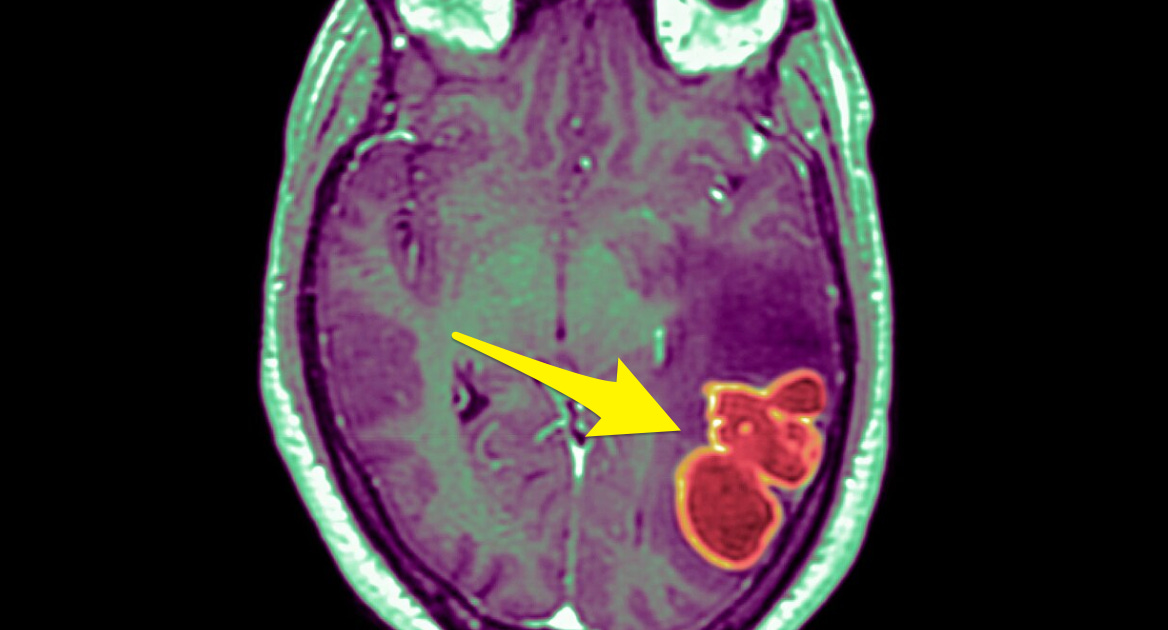

💉 Here we go again! An ABC affiliate in Bakersfield ran a story yesterday headlined, “Mysterious Cluster of Brain Infections Strikes Kids in Nevada.” The sub-headline explained, “In 2022, the number of brain abscesses in kids tripled in Nevada, rising from an average of four to five a year to 18.”

The CDC is investigating another breakout of a previously ultra-rare bug, this time an unusual, fast-onsetting brain abscess. “In my 20 years’ experience, I’ve never seen anything like it,” said pediatric neurosurgeon Dr. Taryn Bragg, an associate professor at the University of Utah who treated the cases.

These kinds of diseases are so rare there is only one pediatric neurosurgeon in all of Nevada. Oddly, the cases started cropping up shortly after the shots were authorized for kids: “After March of 2022, there was just a huge increase” in brain abscesses, Bragg admitted. “I was seeing large numbers of cases and that’s unusual. And the similarities in terms of the presentation of cases was striking.”

The infected children had a median age of 12, and three quarters were boys. Sounds about right.

It’s not just in Nevada, either. Doctors in other parts of the country confirmed they are also seeing similar spikes in pediatric brain abscesses. “We’re just impressed by the number of these that we’re seeing right now,” said Dr. Sunil Sood, a pediatric infectious disease specialist at Northwell Health in New York.

It is kind of hard to estimate how many cases there are, since brain abscesses are not reportable diseases, meaning doctors don’t have to inform public health departments when they find a case. So there could be lots and lots more.

It’s not a minor inconvenience, either. Brain abscesses are pockets of pus-filled infection occurring after bacteria somehow spread into the brain. They cause seizures, visual disturbances, and changes in vision, speech, coordination or balance. (They might want to check Joe Biden’s brain.) The earliest symptoms are like a cold, with headaches and transient fevers.

Abscesses often need several brain surgeries, and kids can spend weeks or months in inpatient hospital care while recovering.

Some of the kids that Dr. Bragg treated needed multiple brain, head, and neck surgeries to clear their infections. Dr. Sood said one patient in his hospital has been there for two to three months and had five surgeries, although Sood said she was an extreme case.

It almost sounds like something somehow induced a kind of immunosuppression in these kids.

Dr. Jessica Penney, a CDC Epidemic Intelligence Service officer, investigated the Nevada cases. Penney said that, as they tried to figure out what was driving the increase, they considered a “slew of factors” — travel, a history of covid infection, underlying health, and any common activities or exposures — and they just couldn’t find ANY common element linking the cases.

Do you, like me, notice something pretty big missing from that “slew of factors” the CDC looked at? Hint: It starts with a ‘v’.

The doctors are, as usual, baffled. They wonder, how are these new infections related to the pandemic? Maybe it’s immunity debt from keeping the kids on lockdown so long? But that doesn’t quite fit either. They don’t know, and they don’t have any good ideas.

Hopefully, the cases will fall again as shots for kids fall, leaving it yet another mysterious post-jab pediatric infection.